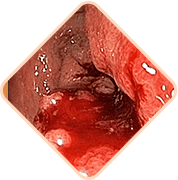

Az aranyér 3 halálosan veszélyes következménye, ha nem kezeli a problémát

A széklet hatalmas mennyiségű mikrobát, baktériumot és gombát tartalmaz. Ha a fertőzés bejut a kismedencei szövetekbe és a szomszédos szervekbe, veszélyes gyulladás és vérmérgezés is lehetséges

Az aranyeres csomók megtelt erei nagyon gyengék. Gyakran szétszakadnak. A vérveszteség mértéke ebben az esetben olyan lehet, hogyvérátömlesztésre is sor kerülhet

Az erekbe vérrögök jöhetnek létre. Ezek a vérrögök leszakadhatnak a vénák falairól és elzárhatják a belső szervekhez vezető ereket, megzavarva így a vérkeringést, és elzárhatják a pulmonalis artériákat.Ebben az esetbne nagy a halál valószínűsége